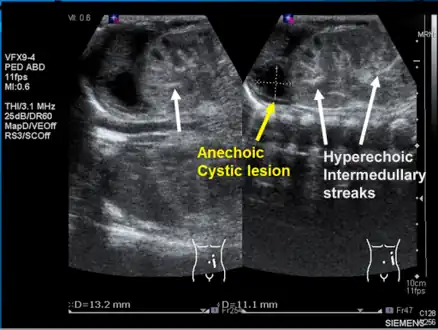

Left kidney with a suprarenal anechoic cyst-like lesion and hyperechoic intermedullary streaks in initial phase of renal vein thrombosis

Observing the patient's symptoms, medical history and imaging remain the fundamental source for diagnosing RVT. Imaging is used to detect the presence of a blood clot. In an abnormal kidney with RVT, a blood clot is present in the renal vein. In cases where the renal vein is suddenly and/or fully blocked, the kidneys will enlarge, reaching its maximum size within a week. An ultrasound imaging can be used to observe and track the size of the kidneys in RVT patients. Ultrasound is not efficient for use in detecting blood flow in the renal veins and artery. Instead a color doppler ultrasound may be used to detect renal blood flow. It is most commonly used to detect RVT in patients who have undergone renal transplantation. CT angiography is currently the top choice in diagnosing RVT. It is non-invasive, relatively cheap and fast with high accuracy. CT scanning can be used to detect renal enlargement, renal tumors, blood flow and other renal pathologies. An alternative is magnetic resonance angiography or MRA. It is non-invasive, fast and avoids radiation (unlike a CT scan) but it is relatively expensive. MRA produces detailed images of the renal blood flow, vesicle walls, the kidneys and any surrounding tissue. An inferior venocavography with selective venography can be used to rule out the diagnoses of RVT.[6]